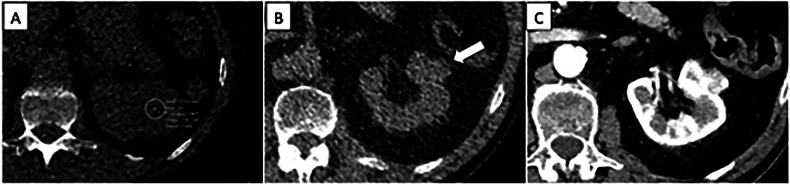

偶然发现(if)在肺癌筛查(LCS)中很常见。虽然发现其中一些发现可导致早期诊断和治疗具有临床意义的病症,但它也有过度诊断和过度治疗的风险,给患者造成焦虑,并增加卫生系统的经济成本。IFs的有效管理需要在明确的指导方针、标准化报告和以参与者为中心的沟通的指导下采取平衡的方法。随着LCS领域的发展,持续的研究和创新对于完善IFs管理策略至关重要,确保筛查的益处最大化,同时将潜在危害降至最低。然而,关于报告和管理IFs的循证指南仍然缺乏。这篇叙述性评论探讨了在LCS报告IFs的利弊,重点是关键争议。重点:肺癌筛查中意外发现的报告和管理存在很大争议。偶然发现的发现可以导致临床重要疾病的早期诊断,但存在过度诊断和过度治疗的风险。必须找到一种平衡,既能对人口产生积极影响,又不会给卫生保健系统带来负担。

Incidental findings (IFs) are common in lung cancer screening (LCS). While the detection of some of these findings can lead to early diagnosis and treatment of clinically significant conditions, it also carries the risks of overdiagnosis and overtreatment, causing anxiety for patients and increased economic costs for health systems. Effective management of IFs requires a balanced approach guided by clear guidelines, standardized reporting, and participants-centered communication. As the field of LCS evolves, continued research and innovation will be essential in refining the strategies for managing IFs, ensuring that the benefits of screening are maximized while minimizing potential harm. Evidence-based guidelines on reporting and management of IFs, however, are still lacking. This narrative review explores the pros and cons of reporting IFs in LCS, focusing on key controversies. KEY POINTS: Reporting and managing incidental findings in lung cancer screening is largely debated. The detection of incidental findings can lead to early diagnosis of clinically significant conditions but carries the risks of overdiagnosis and overtreatment. A balance must be found to have a positive impact on the population while not placing a burden on healthcare systems.